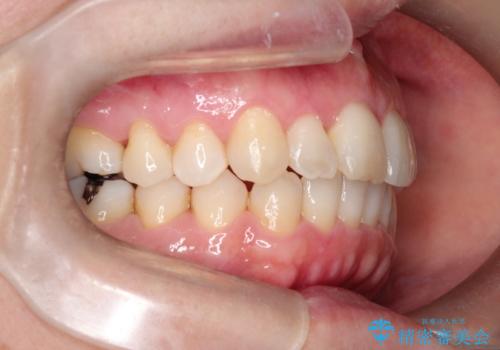

【インビザライン 】前歯のガタガタを治したい

- 前歯のガタガタを主訴に来院されました。

インビザライン で治療しました。途中は使用時間が20時間を切ることもありましたが、それでも頑張って使っていただき1年半で矯正終了することができました。